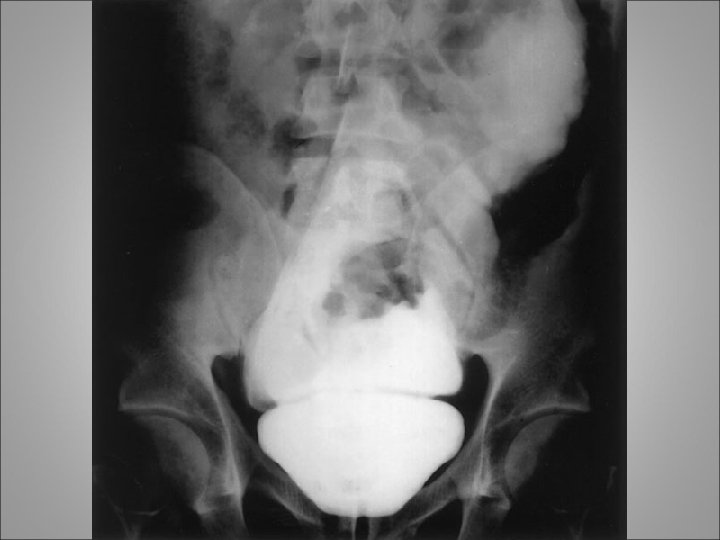

BLADDER INJURIES • The urinary bladder is well protected from external trauma by the bony confines of the pelvis • The majority results from blunt trauma which include motor vehicle accidents, falls and assaults • They are frequently associated with multiple organ trauma, with an average of three coexisting organ injuries and a mortality rate of 20% • Absolute indications for bladder imaging after blunt abdominal trauma are currently limited to two indications: (1) the presence of gross hematuria coexisting with a pelvic fracture and (2) inability to void

BLADDER INJURIES • Traumatic bladder lacerations in children are approximately two times more likely to extend through the bladder neck compared with adults • The diagnosis of a traumatic bladder injury should be assessed by either standard or CT cystography • The amount instilled within the bladder should, at a minimum, be equal to one half of the estimated bladder capacity for age • All patients with traumatic bladder lacerations, either extraperitoneal or intraperitoneal, should initially be treated with intravenous antibiotics with oral antibiotic therapy continued for 48 hours after removal of bladder catheters

Intra and extra peritoneal bladder rupture

BLADDER INJURIES • In extraperitoneal bladder injury, consideration for open surgical intervention should be given if a bony spicule is found to protrude into the bladder on CT evaluation or if concern for a bladder neck laceration is present • If these two complications are not present, management by an indwelling urethral catheter can be considered • Urinary drainage via the bladder catheter is maintained for 7 to 10 days, and a cystogram should be obtained to verify healing of the injury before catheter removal • In intraperitoneal bladder injuries, open surgical repair of the laceration is the recommended treatment modality